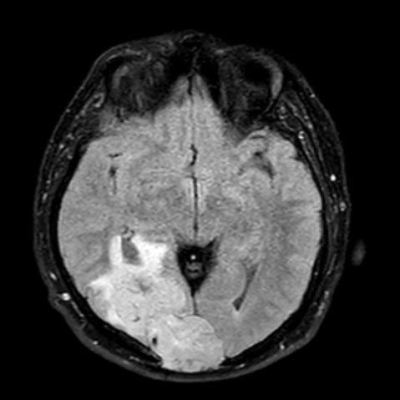

44 yaş, E

Baş ağrısı

hemorajik glioblastoma multiforme (GBM, WHO Grade 4)